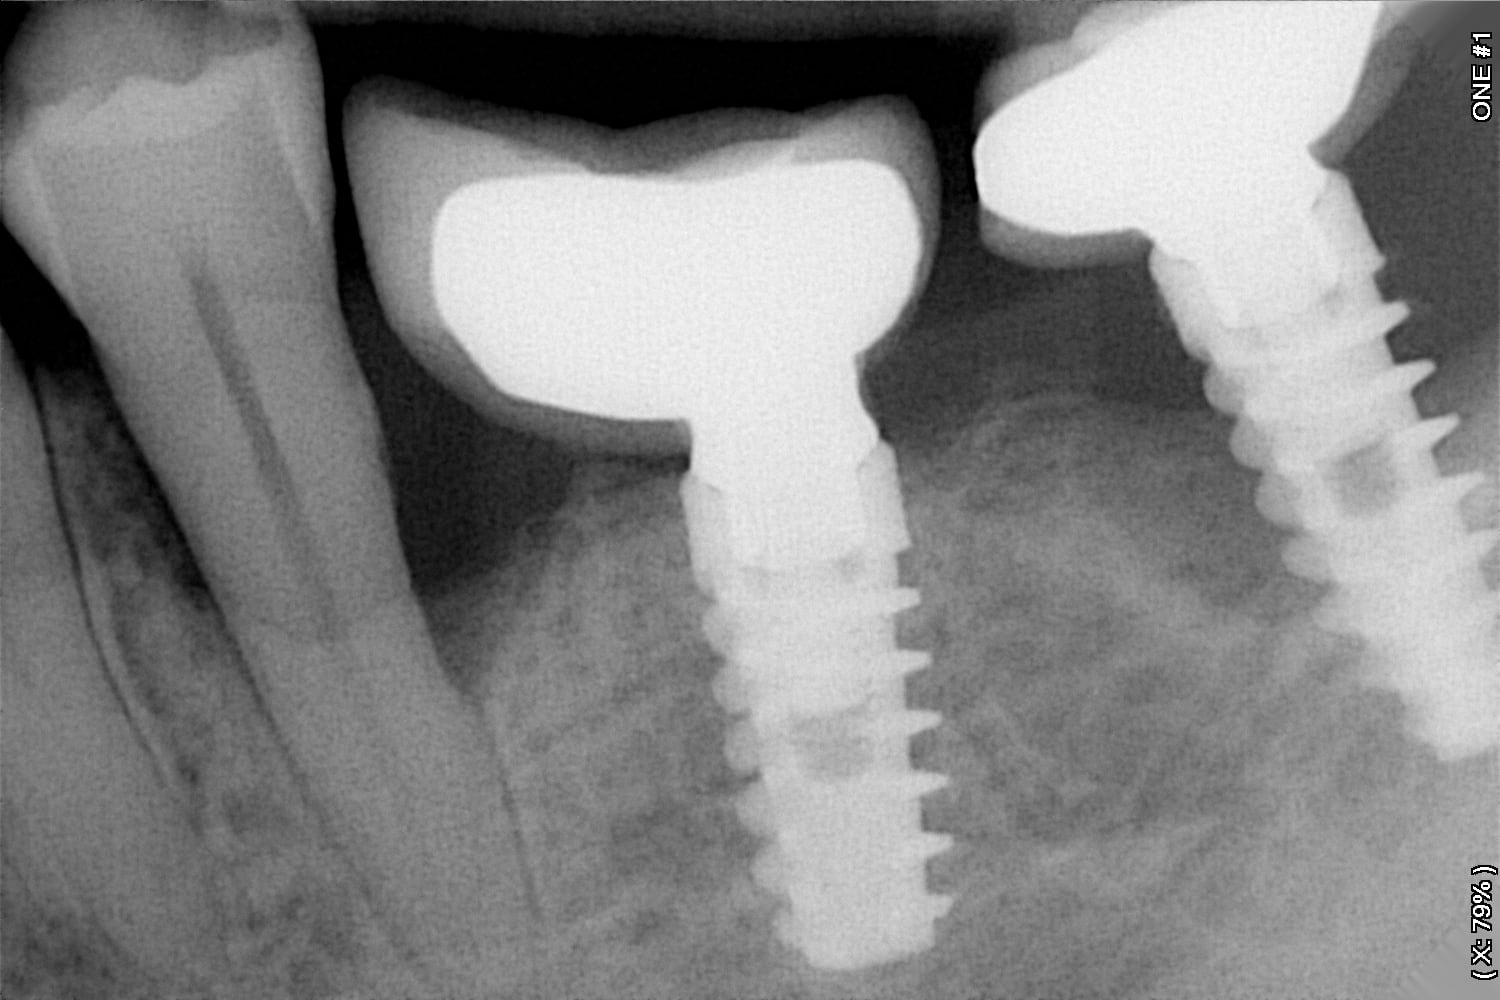

Sur la rétro, implant spirale type alpha bio

là comme çà en premier jet, un Biomet

https://www.spotimplant.com/fr/implants-dentaire/biomet-3i/full-osseotite-xp-certain5